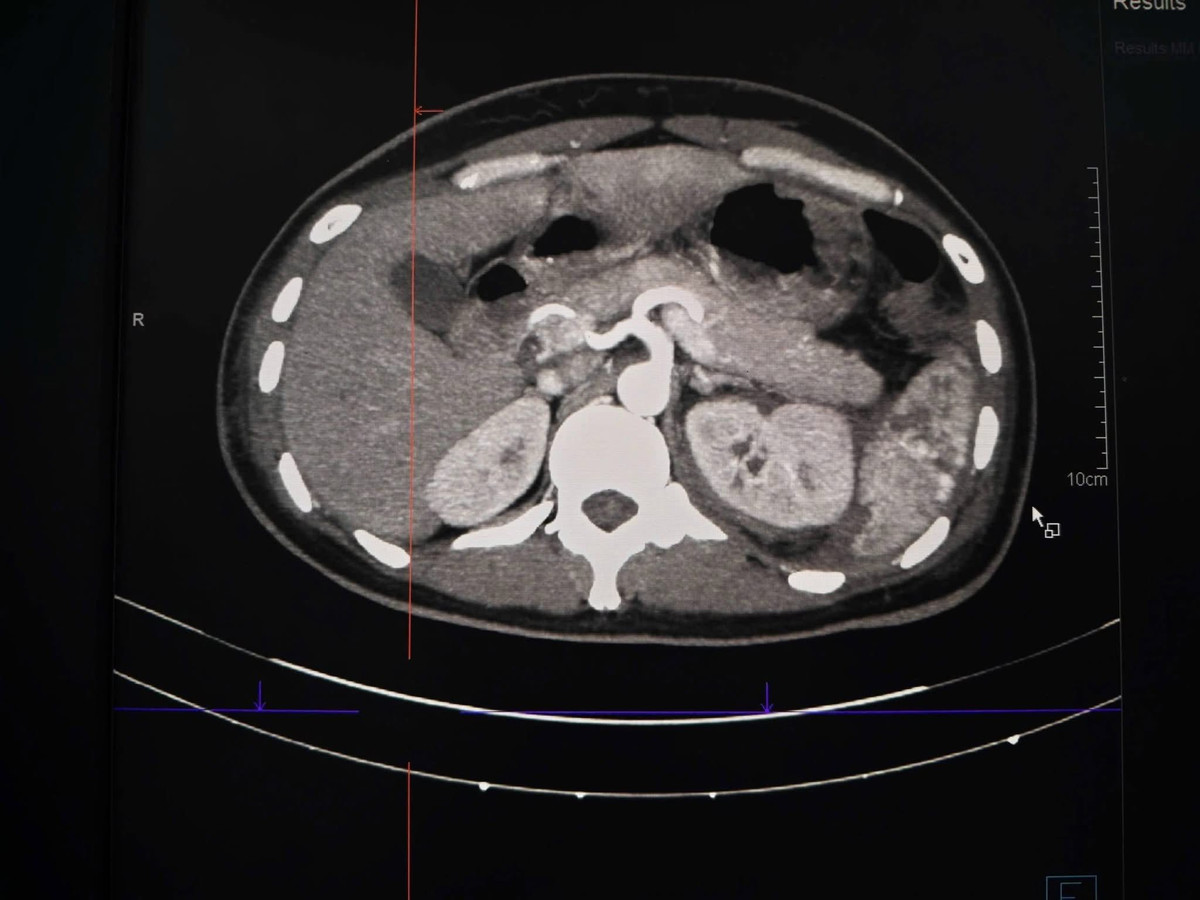

Hình ảnh thận và lách vỡ trên phim chụp - Ảnh BVCC

Kết quả chụp CT cho thấy tổn thương rất nặng: vỡ lách phức tạp, vỡ thận độ IV có giả phình mạch và chảy máu hoạt động, kèm tràn máu ổ bụng. Tình trạng này có thể gây sốc mất máu bất cứ lúc nào nếu không xử trí khẩn cấp.

Sau hội chẩn nhanh giữa Cấp cứu – Ngoại tổng hợp – CĐHA, các bác sĩ nhận định tổn thương mạch máu khu trú, phù hợp ưu tiên can thiệp nội mạch cầm máu nhằm tránh một cuộc mổ lớn nhiều rủi ro.

Tại phòng can thiệp mạch, dưới hệ thống chụp mạch số hóa xóa nền (DSA), các bác sĩ Khoa Chẩn đoán hình ảnh xác định điểm chảy máu và giả phình ở cả lách và thận, sau đó tiến hành nút tắc các nhánh mạch tổn thương. Toàn bộ thủ thuật diễn ra trong khoảng 45–60 phút.